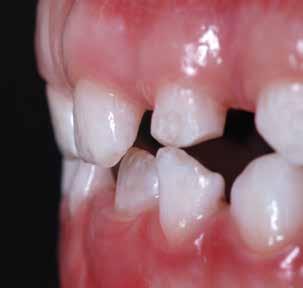

Presentazione del caso > F.V, bambino di cinque anni, presenta una malocclusione di II Classe scheletrica, III Classe dentale molare e canina destra e sinistra, morso inverso anteriore. Le arcate dentali mostrano usura degli elementi dentari anteriori a causa dell’occlusione patologica. Le linee mediane, superiore ed inferiore, sono centrate; il frenulo labiale superiore patologico per un’eccessiva estensione inter-incisale.

Il piano di trattamento prevede l’utilizzo di un dispositivo elastodontico di III Classe, da portare per due ore diurne e tutte le notti in modo passivo, senza effettuare alcun esercizio, al fine di ripristinare una relazione molare e canina bilaterale di I Classe ed il corretto avanzamento maxillare e inibire l’eccessiva crescita mandibolare. È possibile ottenere il risultato in pochissimi mesi di terapia, essendo la crescita del paziente molto attiva.

In un secondo momento, alla risoluzione della problematica scheletrica, si monitorizzerà il caso con visite semestrali in modo da reintervenire qualora si dovesse ripresentare la problematica.

Dall’esame clinico si evince la III Classe dentale, l’inversione anteriore e l’over-jet negativo.

Una volta ottenuta la correzione del rapporto molare ed incisale, l’apparecchio elastodontico verrà portato dal paziente solo durante la notte per stabilizzare il risultato ottenuto e guidare l’eruzione degli elementi dentari per un totale di quattordici mesi di terapia. ad inizio trattamento :

Considerazioni > L’analisi cefalometrica ad inizio trattamento dimostra la II Classe scheletrica con protrusione del mascellare superiore e prognazia mandibolare; tendenza alla crescita verticale. L’esame clinico evidenzia una protrusione mandibolare funzionale.